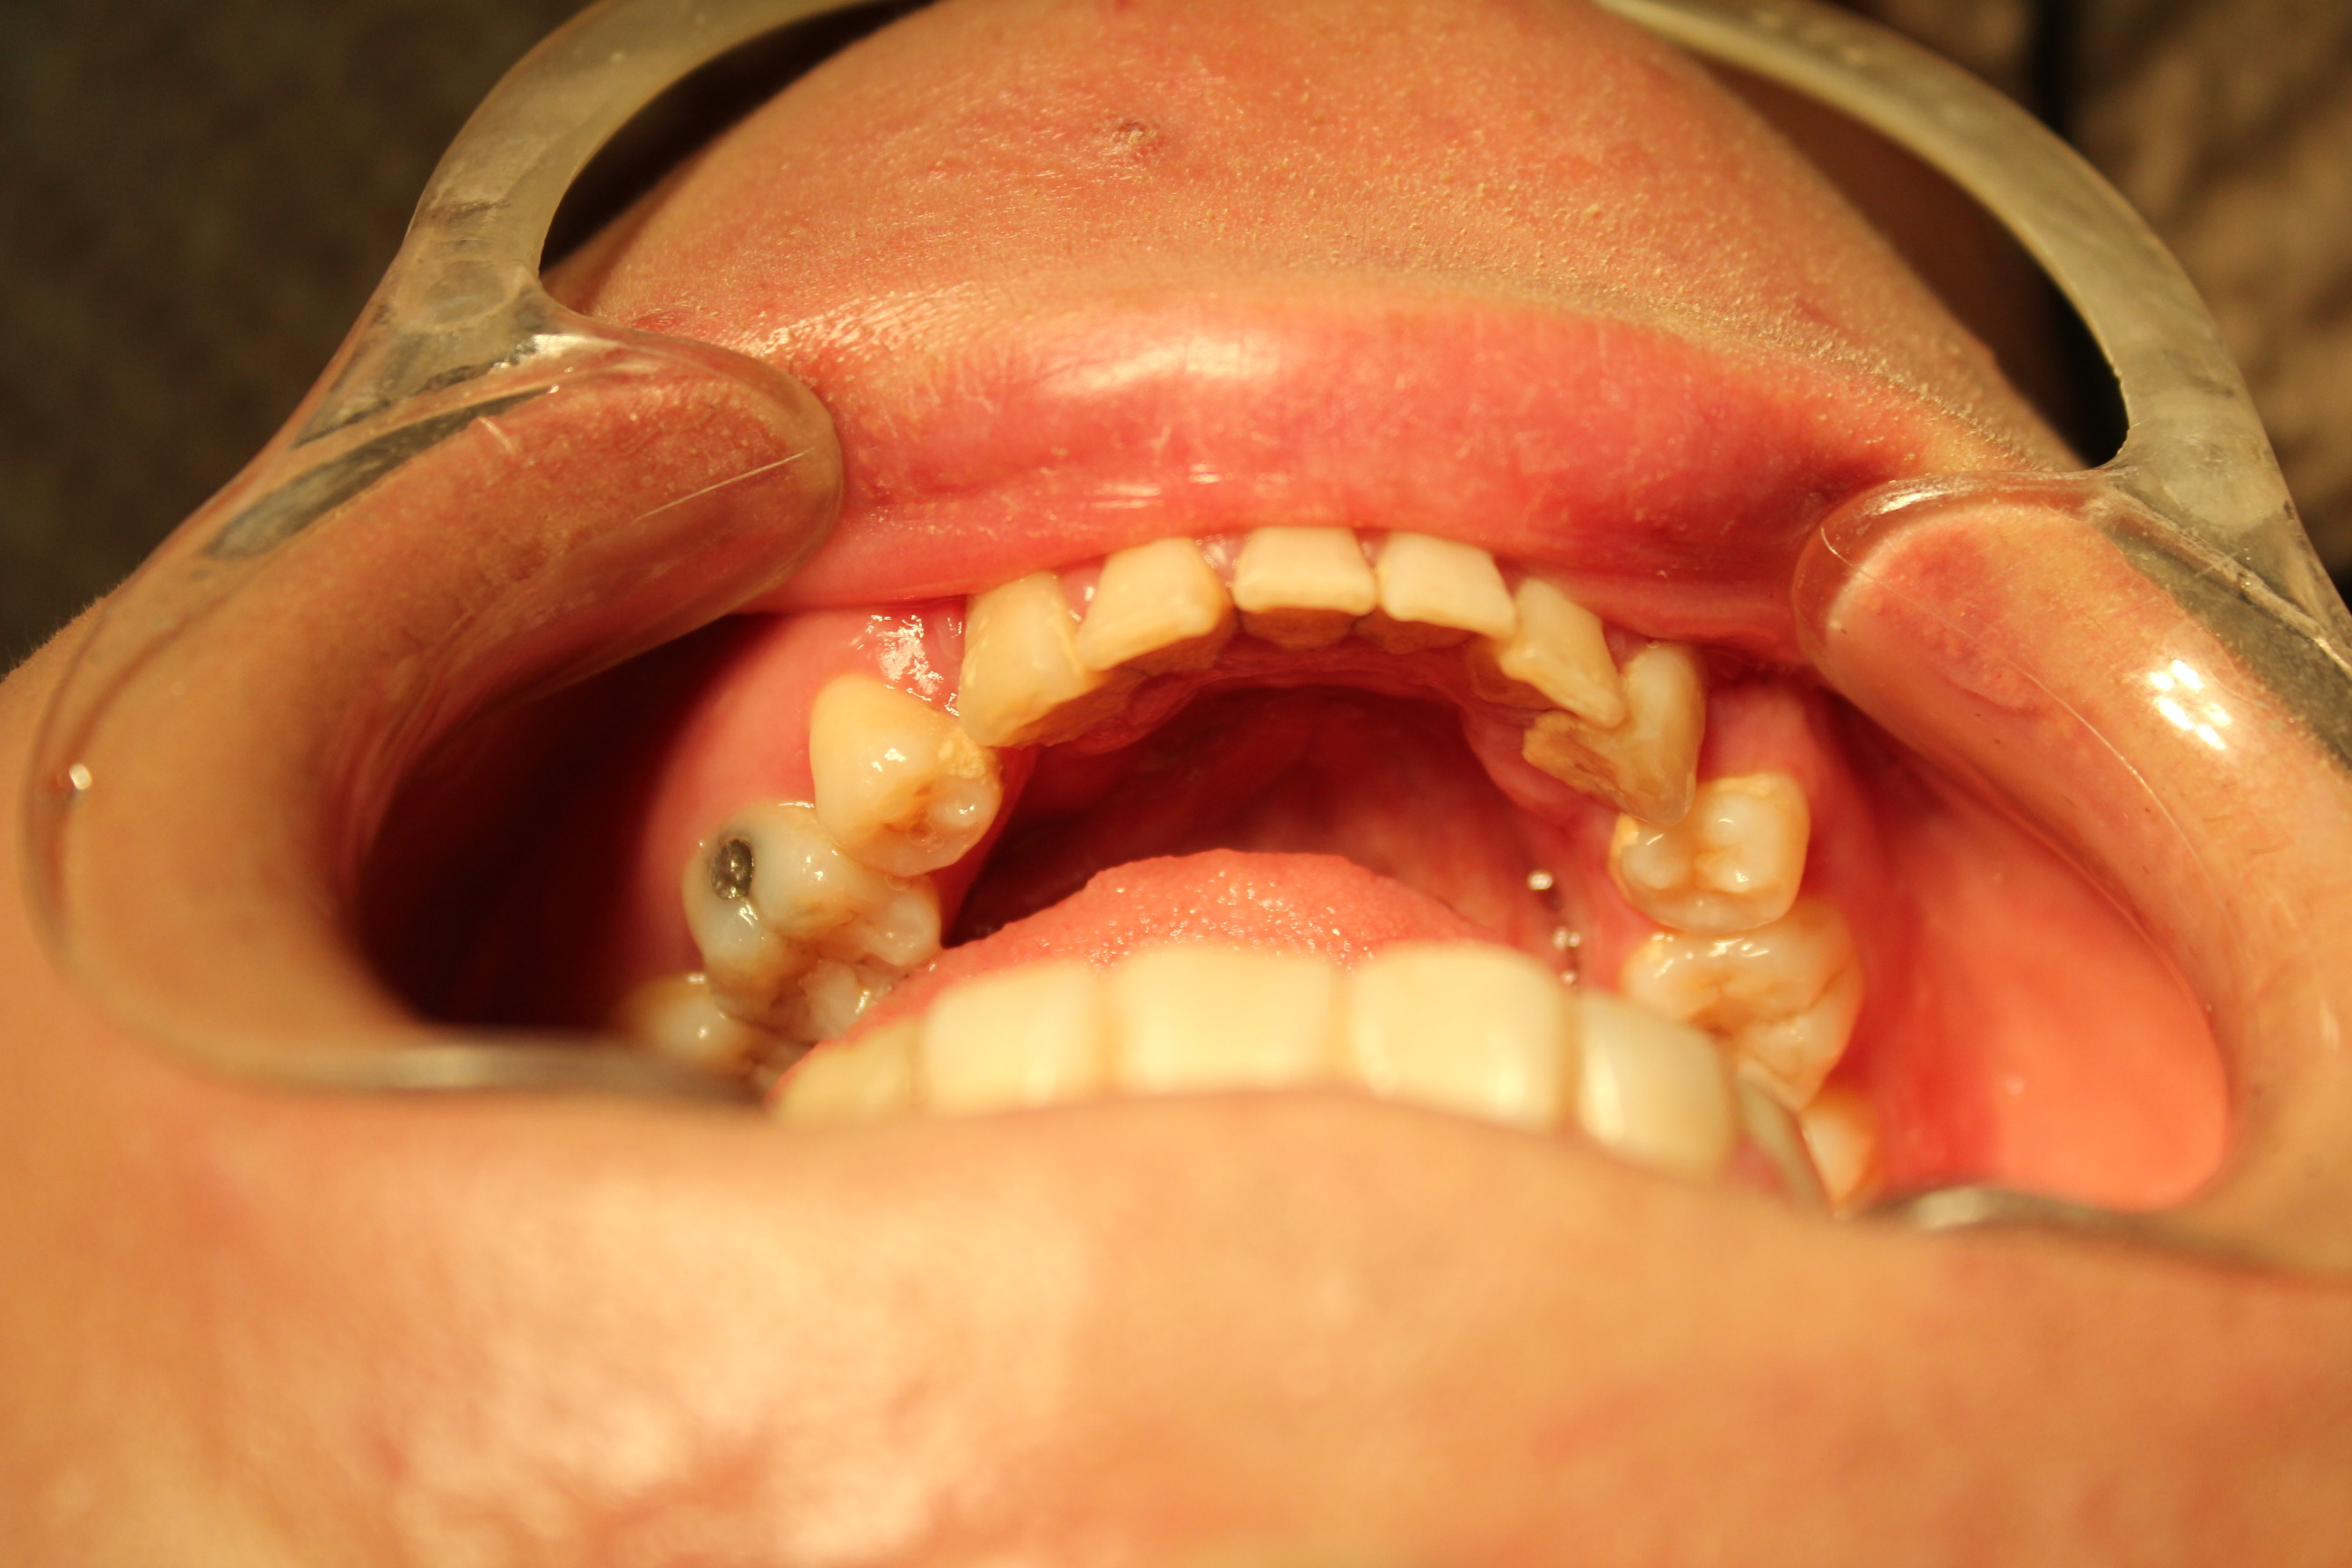

돌출입 수술후 치아 교정 와이어 제거후 (5개월째) - 하악치아상태

돌출입 수술후에 바로 치아교정 장치 를 달지 않고도

수술전 교합 웨이퍼 이용한 올바른 돌출입 수술에서는 발치 부위 와이어 고정으로도 올바른 치열을

얻을수 있다.

다만, 악궁은 좁아지기 때문에 드물게 치열이 벌어지는 현상이 올때는 교정이 필요합니다.